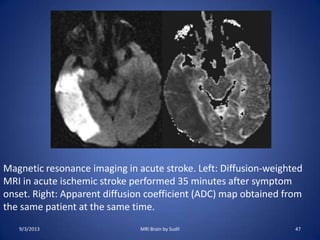

Magnetic resonance imaging in acute stroke. Left: Diffusion-weighted

MRI in acute ischemic stroke performed 35 minutes after symptom

onset. Right: Apparent diffusion coefficient (ADC) map obtained from

the same patient at the same time.

9/3/2013 47MRI Brain by Sudil